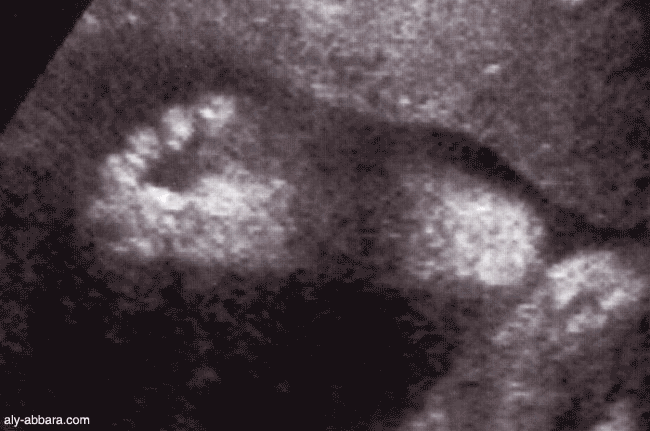

Coupe échographique montrant les détails d'un pied d'un fœtus à 30 SA

les cinq orteils et la face plantaire du pied